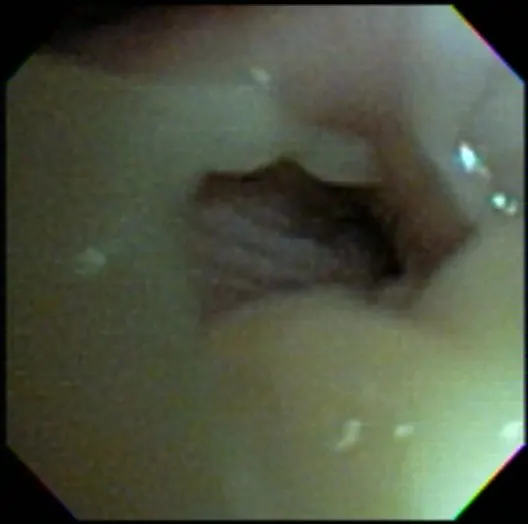

On examination, the dog was panting with expiratory effort and crackles auscultated diffusely. She exhibited an occasional goose-honking cough and retch. Her body temperature was normal. Radiography (Figures 1 and 2), fluoroscopy (Figure 3), and bronchoscopy (Figures 4 and 5) were performed.

Bronchoscopy revealed moderate grade 2 (40%-50%) extra-thoracic airway collapse, with grade 4 (100%) collapse of the intrathoracic airway (most severe at the carina). Marked diffuse purulent discharge was observed throughout the trachea and mainstem bronchi along with grade 3 to 4 (75%-100%) collapse of proximal bronchi (left cranial, right cranial, and right middle), with thickened mucosa and blunted airway divisions throughout. The caudal airways (left and right) were less affected distally.